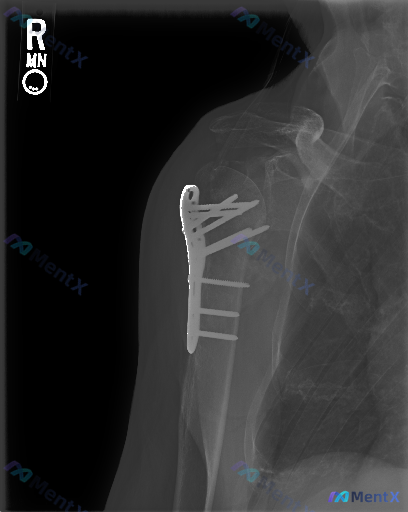

整理到一份右肩术后的Y位X光片分析,有点意思,不是典型的“一目了然”型病例。 先把核心影像表现列出来: - 右肩肩胛骨斜位(Y位)投照,肱骨近端外侧有解剖锁定钢板+多枚螺钉固定 - 内固定物看着位置还行,没有明显的断裂、松动 - 肱骨近端(外科颈+结节区)有陈旧性骨折痕迹,骨折线模糊,但骨痂形成不甚...